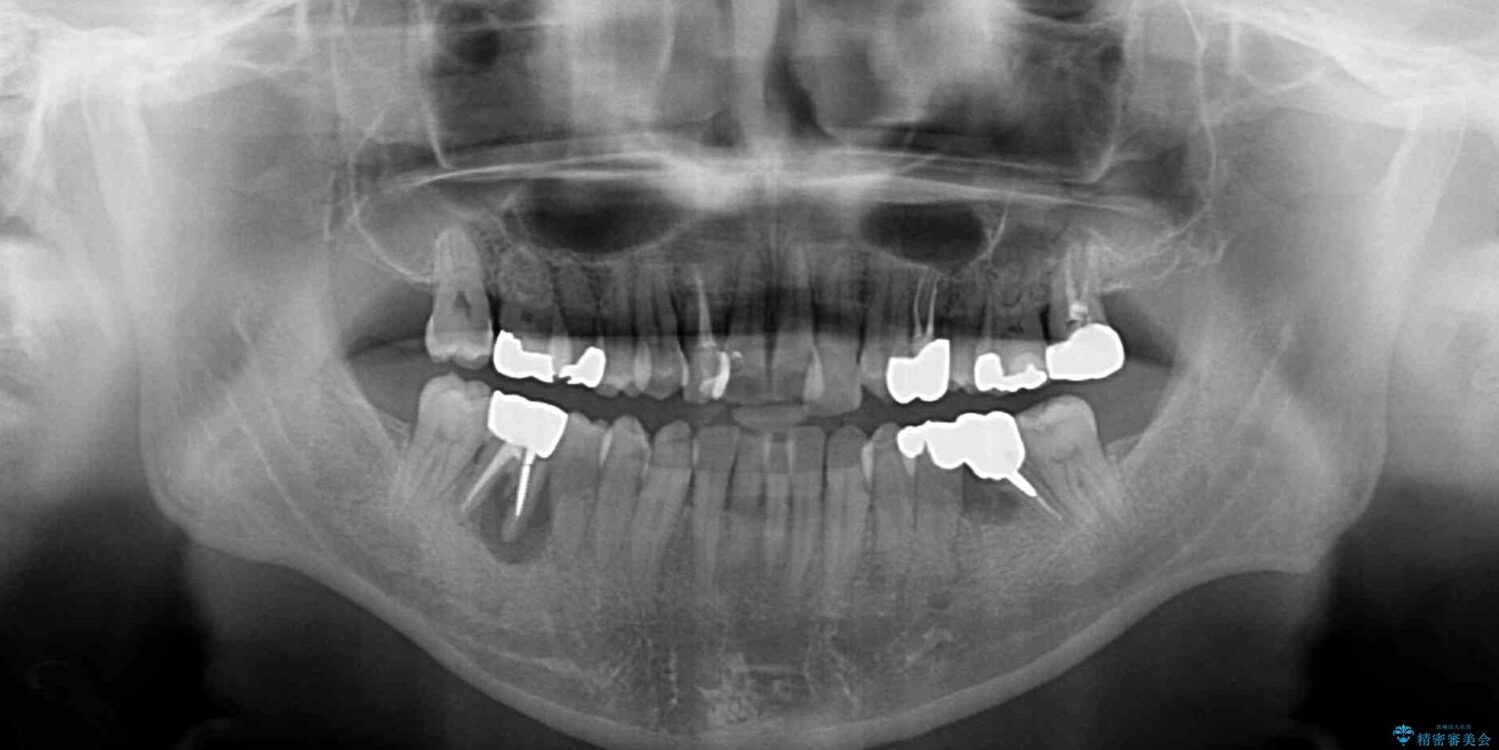

左右下顎の大臼歯は、ともに歯根が破折しており、抜歯が必要な状態でした。

放置したことで炎症による骨吸収が顕著であるため、骨造成を併用してインプラント埋入を行うこととしました。

咬み合わせは受け口傾向であり、上顎前歯の叢生が顕著であったことから、第1小臼歯抜歯による矯正治療も検討しましたが、下顎大臼歯を左右ともに抜歯するため、非抜歯による矯正治療を行うこととしました。

矯正治療でインプラント埋入を行い、矯正治療後に気になる前歯と合わせてオールセラミッククラウンによる補綴治療を行うこととしました。

骨造成や歯肉移植など、治癒期間の長い処置を必要としたため治療期間は長くなりましたが、安定した咬み合わせと整った歯列となり、患者様には大変満足していただきました。